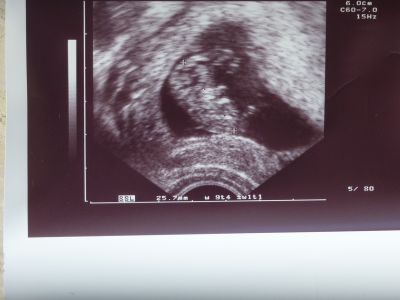

Meine Gynäkologin würde jetzt sagen: "Sie sind ja so was von schwanger!"conny74 hat geschrieben: Ich habe extremen Heißhunger, bin ziemlich schnell aus der Puste und manchmal von total zickig bis total nah am Wasser gebaut....aber ansonssten geht es mir gut